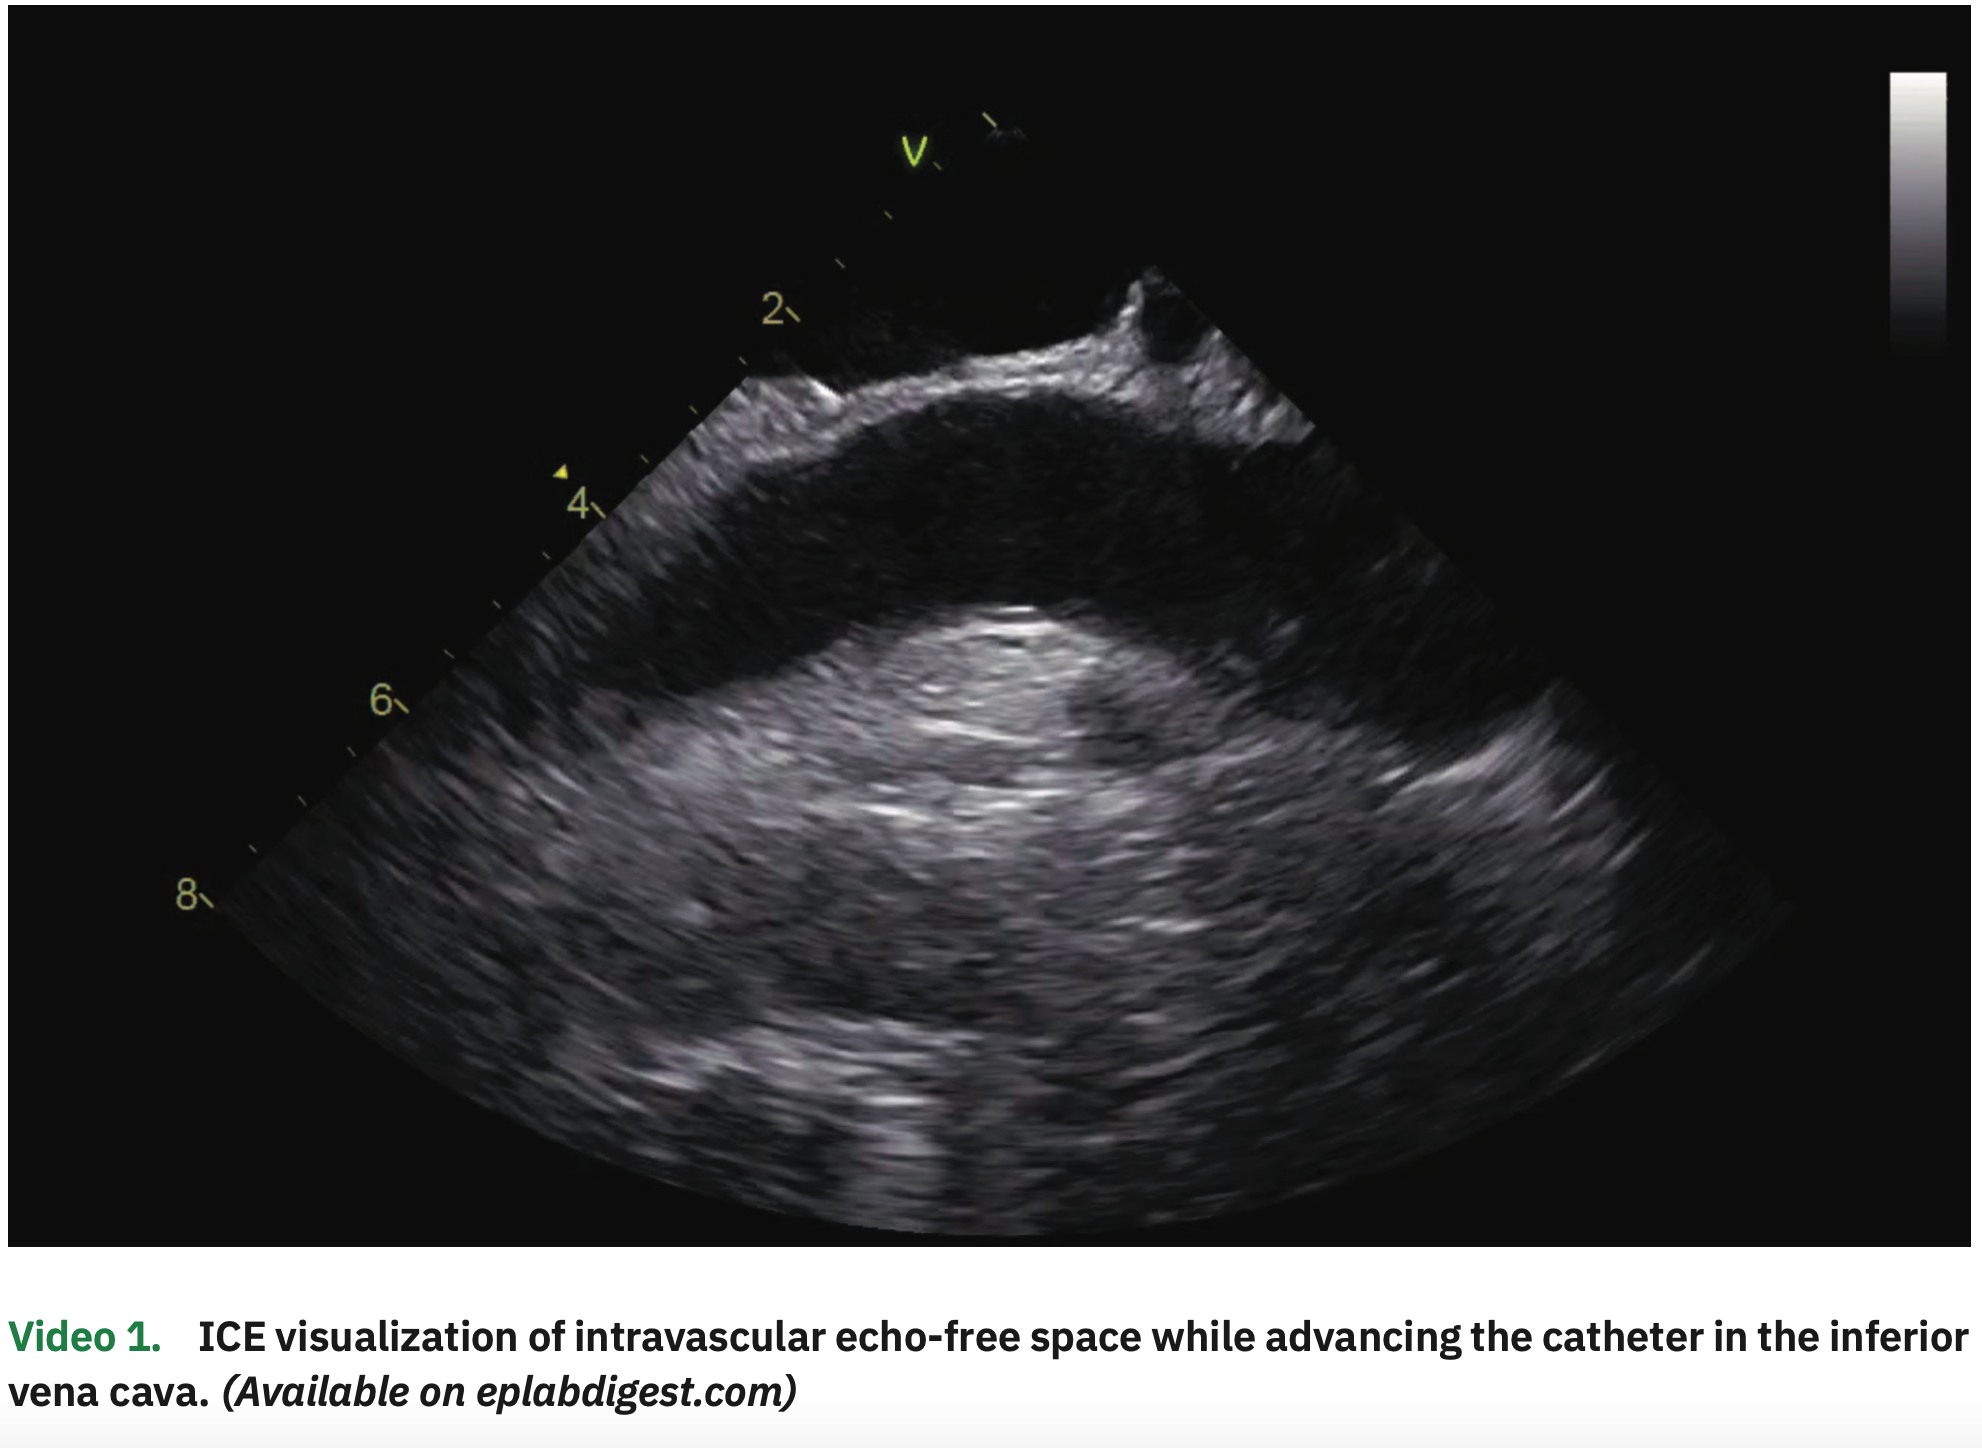

The procedure was performed under general anesthesia and on uninterrupted apixaban (last dose in the evening before the early morning procedure). The patient was in paced rhythm both in the atrial and ventricular channels. Venous access was obtained in the right and left femorals as well as in the right internal jugular vein, all guided by ultrasound. From the left femoral vein, an ICE catheter was advanced to the right atrium (RA), guided by visualization of echo-free spaces in the vascular system (Video 1). The pacemaker leads were clearly visualized in the RV septum and right atrial appendage (Figure 1 and Video 2). A multipolar esophageal catheter was placed and its position guided by ICE visualization.